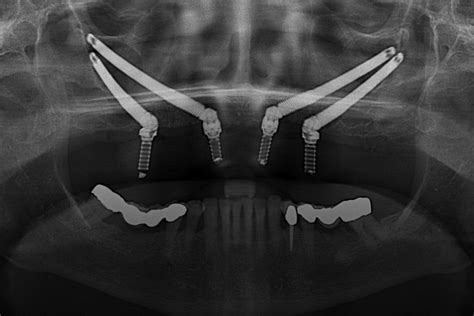

En el ámbito de la Implantología, se trata de un centro de referencia en la colocación de implantes en casos complejos. En estos casos los tratamientos no solo consisten en la colocación de los implantes, sino que se tienen que realizar tratamientos complementarios como son los injertos óseos, de tejido conectivo o elevaciones de seno, entre otros.

Cabe destacar que el centro está especializado en la realización de tratamientos con implantes cigomáticos, así como en la cirugía periimplantaria.

Implantes Cigomáticos: Una solución avanzada para casos complejos.